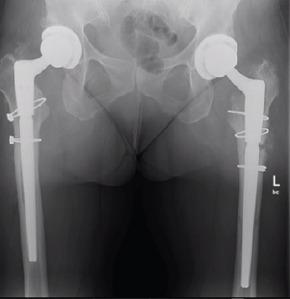

A 48-year-old female underwent bilateral staged primary THA with fully porous-coated anatomic medullary locking femoral prostheses. She subsequently sustained stem fractures of her right and left prostheses in the 13thand 14thyears after their implantation, respectively.

一名48岁女性接受了双侧分期初次全髋关节置换术,使用的是全多孔涂层解剖型髓内锁定股骨假体。随后,她在植入假体后的第13年和第14年分别发生了右侧和左侧假体的柄部骨折。